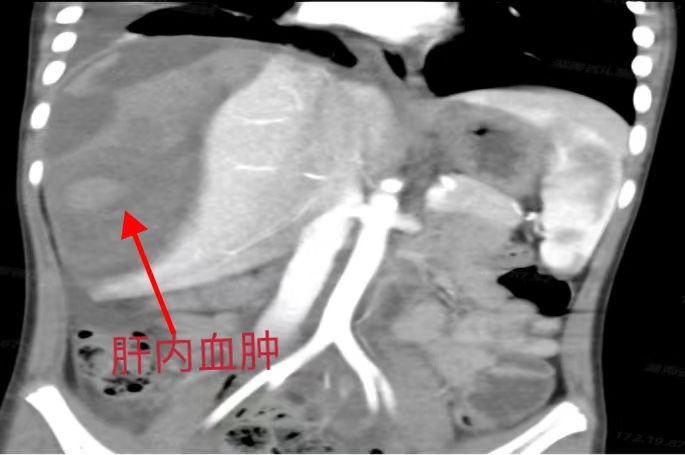

成成入院时病情十分危重,肝脏受损面积大,右侧肝脏几乎“破碎”,且循环血量不稳定,随时有肝脏破裂大出血的危险。完善检查后成成诊断为肝挫裂伤(AAST 5级)。

儿童肝脏因其独特的解剖生理性特点,一般情况下儿童肝外伤的程度相对轻微,在临床处理时更倾向于保守治疗。但成成的情况属于重度肝损伤,肝挫伤范围大,伴有肝脏重要血管的损伤,随时可能出现血肿破裂出血,危及生命,需要接受手术治疗进行破损肝脏的清创、止血。通过精准实施手术,尽可能多地为成成保留正常肝组织以维持其生理功能,该手术程序复杂、难度系数高,对术者的操作技巧及手术经验也要求极高。